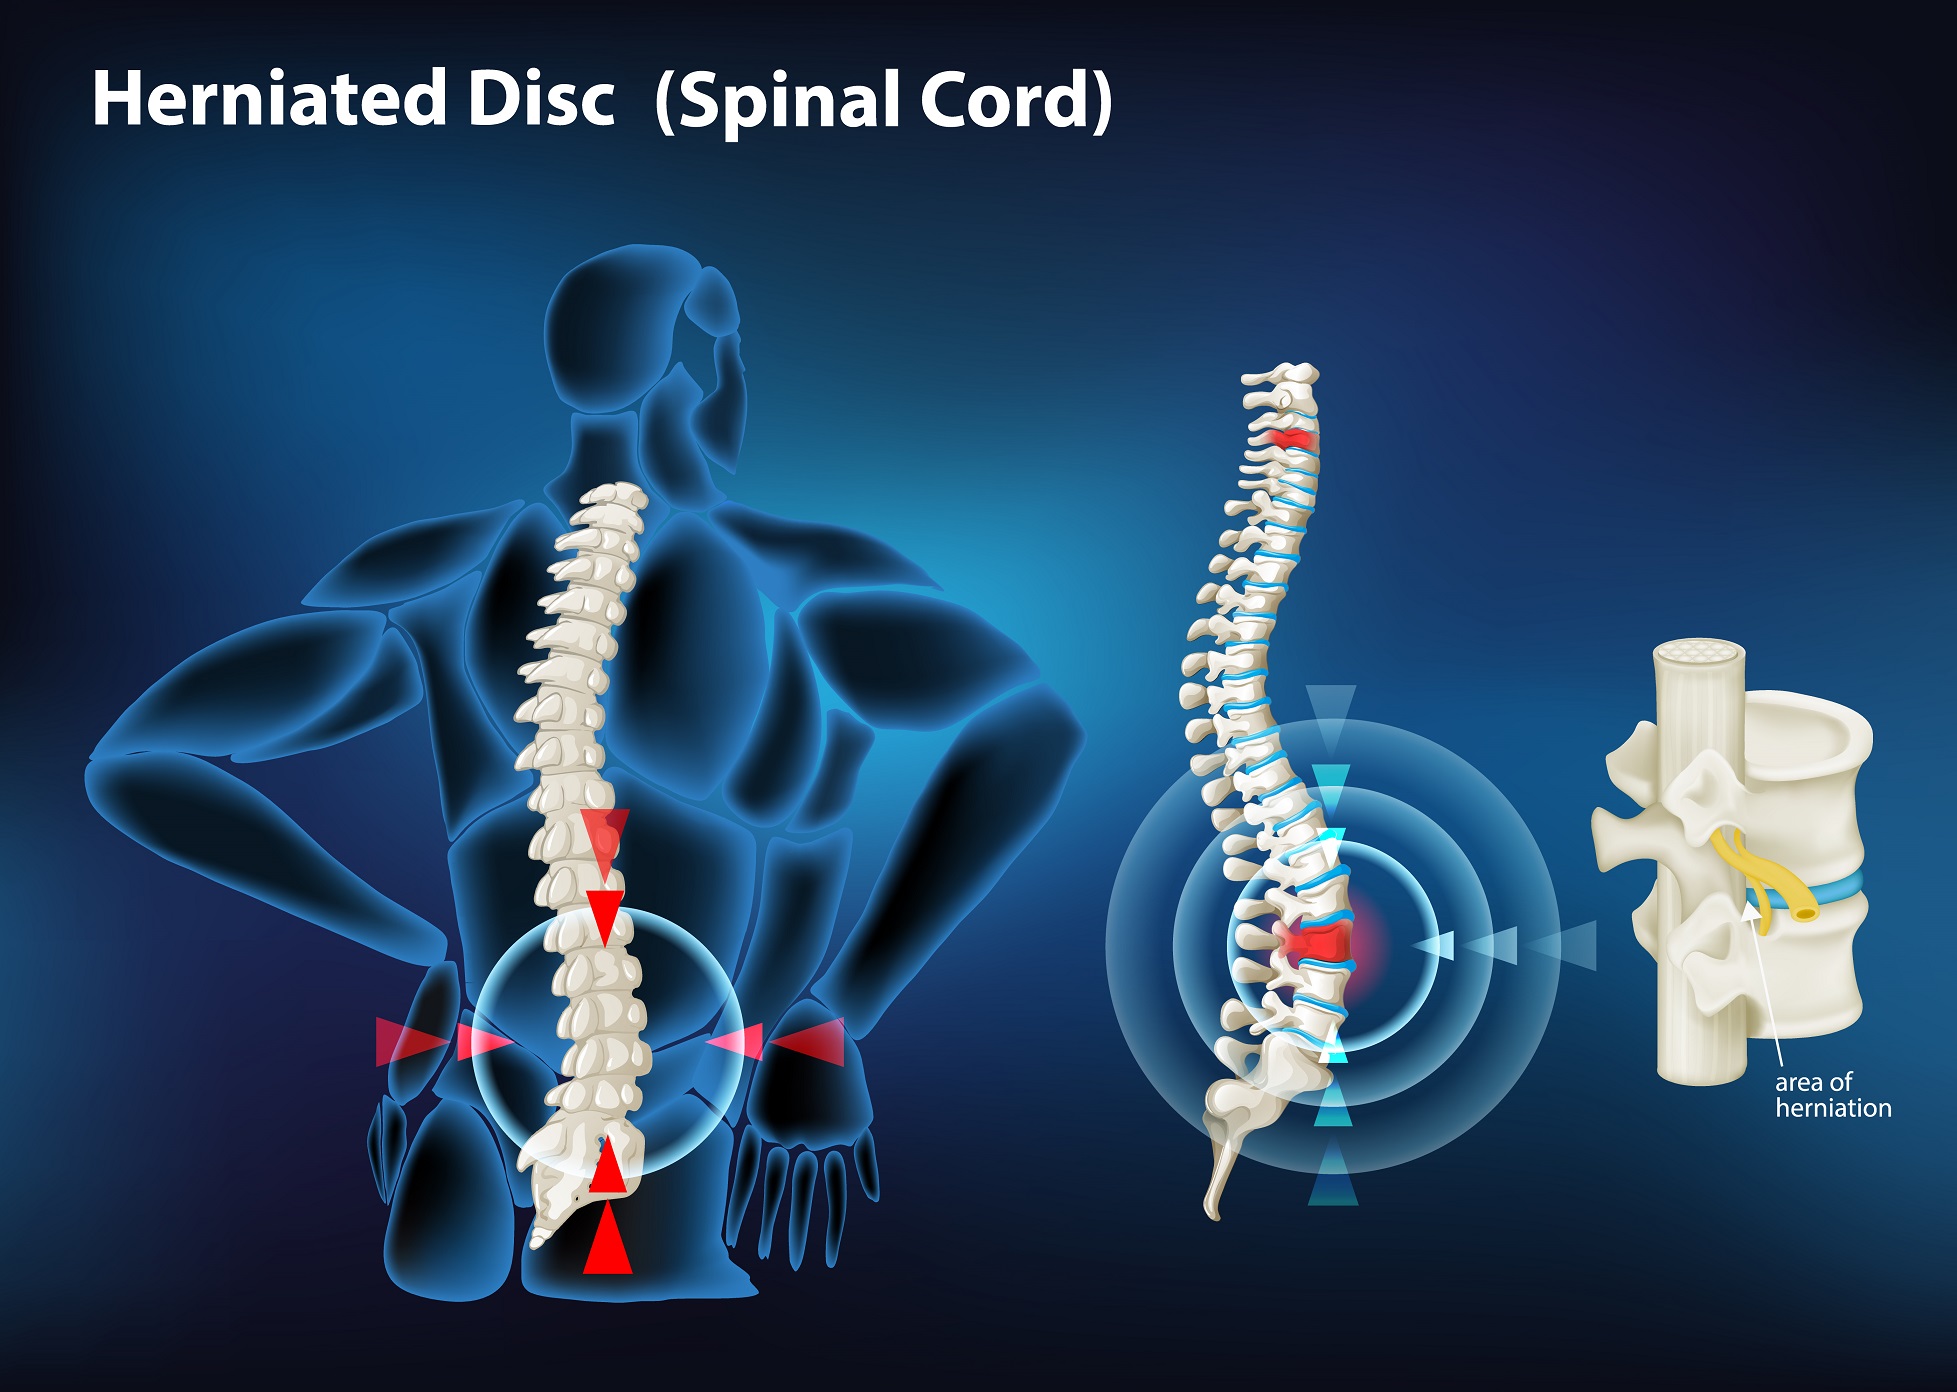

- Facet Block Injections